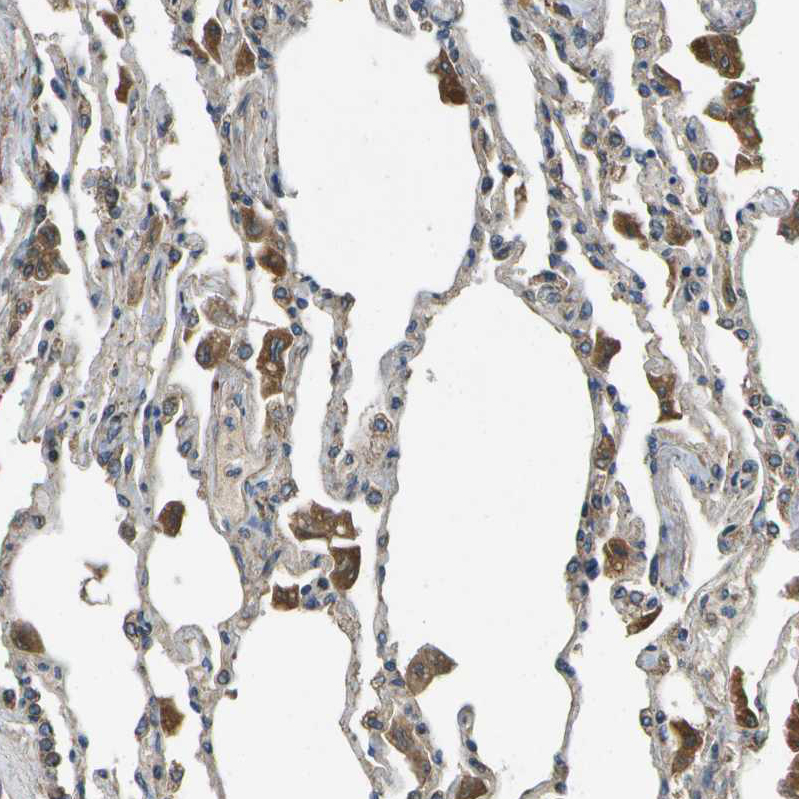

Immunohistochemical staining of human urinary bladder shows strong cytoplasmic positivity in urothelial cells.